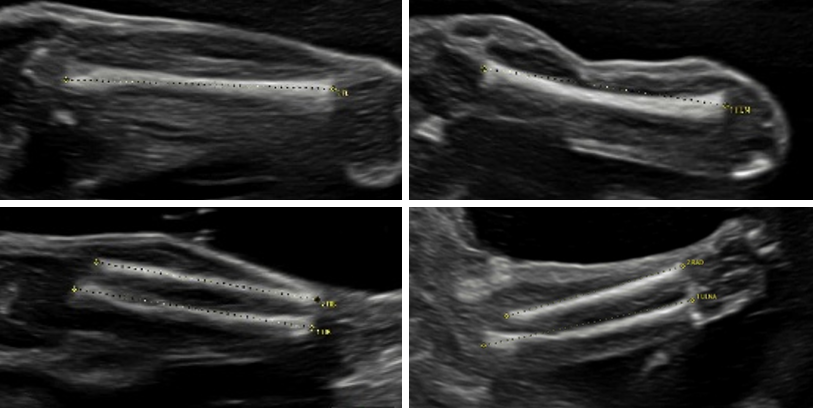

„Feindiagnostik“: 20-24 SSW

Wir schauen Ihr Kind im Ultraschall detailliert von Kopf bis Fuß an. Mit Fortschreiten der Schwangerschaft liegt der Fokus hier besonders auf der Entwicklung von Herz und Kopf Ihres Kindes. So können wir Besonderheiten frühzeitig erkennen, die Schwangerschaft optimal begleiten und die Geburt bestmöglich vorbereiten. In manchen Fällen ist eine Behandlung bereits während der Schwangerschaft möglich.

Je nach Fragestellung kann diese Untersuchung auch zu einem deutlich früheren oder späteren Zeitounkt sinnvoll sein.